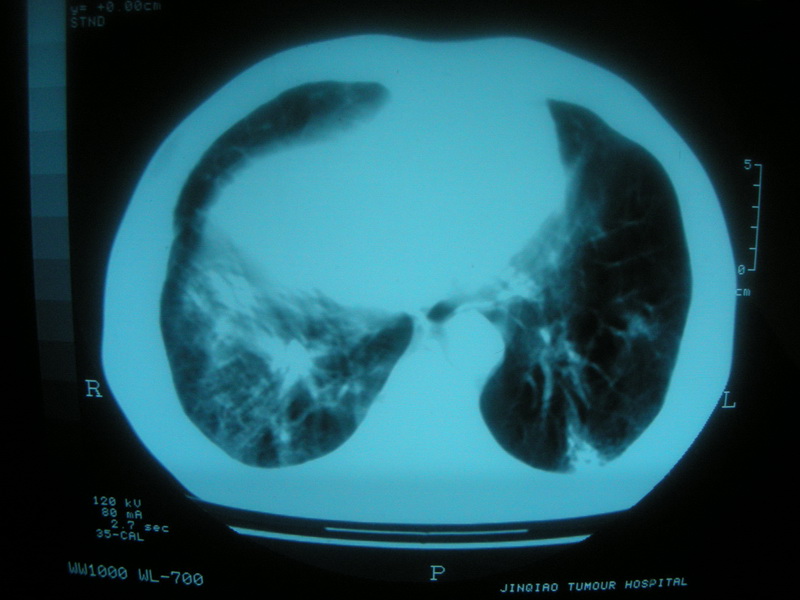

标题: CT11692:男,63岁,糖尿病史15年.抗炎治疗7天,病情 [打印本页]

标题: CT11692:男,63岁,糖尿病史15年.抗炎治疗7天,病情

请老师看看是结核还是炎症?

根据影像表现及临床符合结核感染。

双肺继发性肺结核伴感染!

双肺继发性肺结核伴支气管播散。